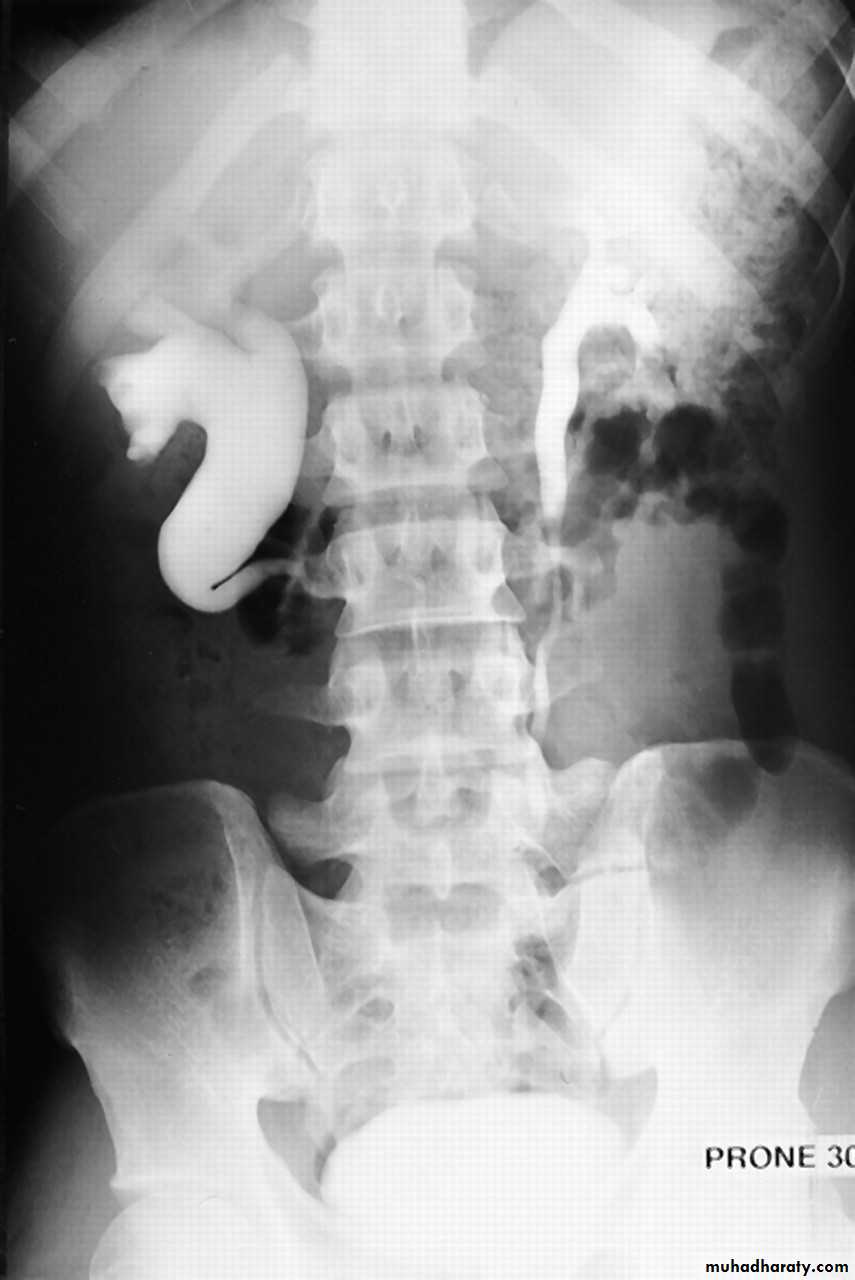

Retrocaval ureter:- (right ureter ) behind inferior vena cava.

*PUJ obstruction&retrocaval ureter